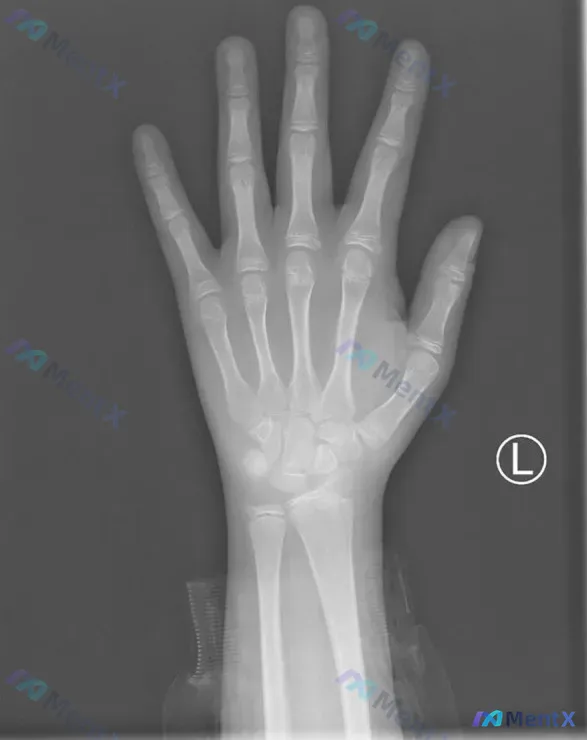

最近看到一张左手腕的骨龄片,整理一下思路,和大家一起探讨分析逻辑。 一、先看病例基本影像资料 这是一张标记为L的左手正位X光片,投照体位基本符合标准,手指自然平展,掌骨、指骨及腕关节显示完整。 关键阳性与阴性信息: ✅ 骨皮质:各指骨、掌骨、腕骨的骨皮质连续光整,未见中断、骨折线或骨痂 ✅ 骨小梁:...